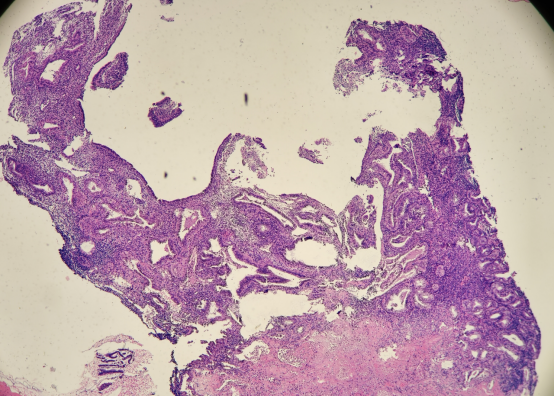

HE染色切片:

免疫组化结果: